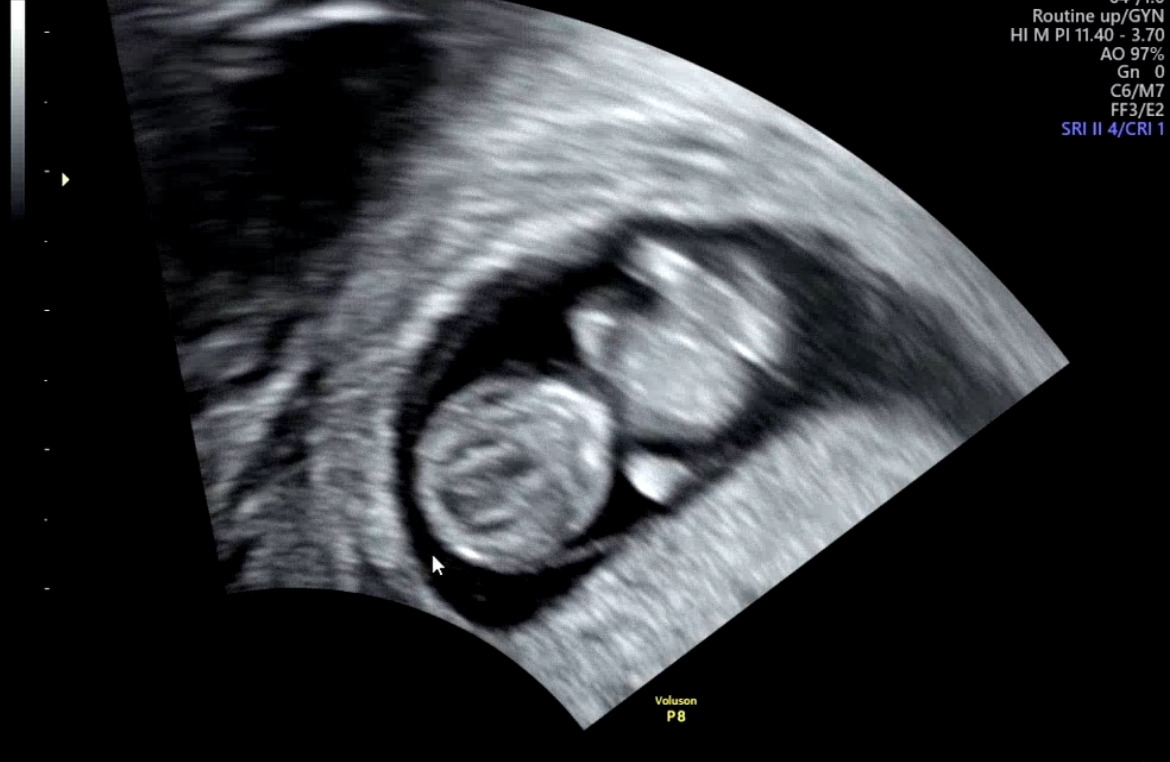

2024년 11월 13일. 한 달 전에 아기집을 확인하고 2주 전에는 너의 심장 소리도 잘 듣고 왔단다. 오늘은 네가 또 얼마나 많이 컸는지 엄마 몸에는 문제가 없는지 이것저것 확인을 하러 가는 날이었어. 아 오늘은 처음으로 라온이도 함께 널 보러 가는 날이었는데.. 저번에 보건소에서 받은 산전검사에 조금 문제가 있다고 하네.

아직 9주밖에 안된 네가 오늘은 엄마 뱃속에서 어찌나 많이 움직이던지. 집에 가면 아빠랑 라온이랑 그 모습이 담긴 너의 영상을 몇 번이고 돌려보려 했는데.. 이 마음이 너무나도 무거워서 그 이후로는 더 이상 너의 모습을 볼 용기가 나지 않더라.